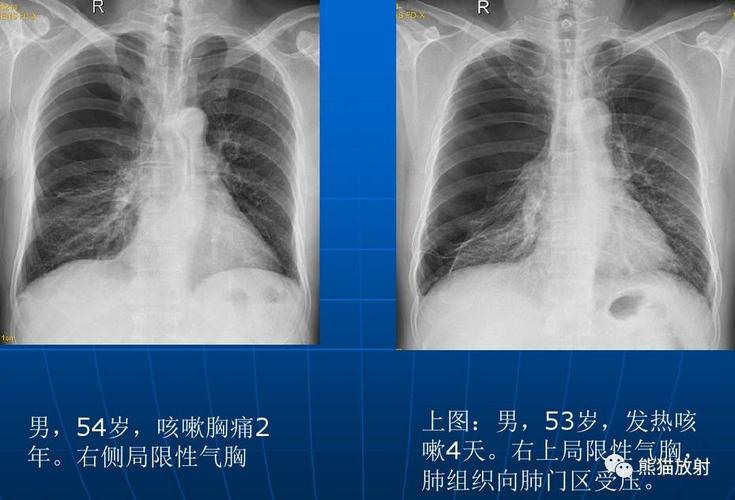

气胸x线胸片典型表现

气胸胸片

气胸的x线表现

气胸的x线表现图片